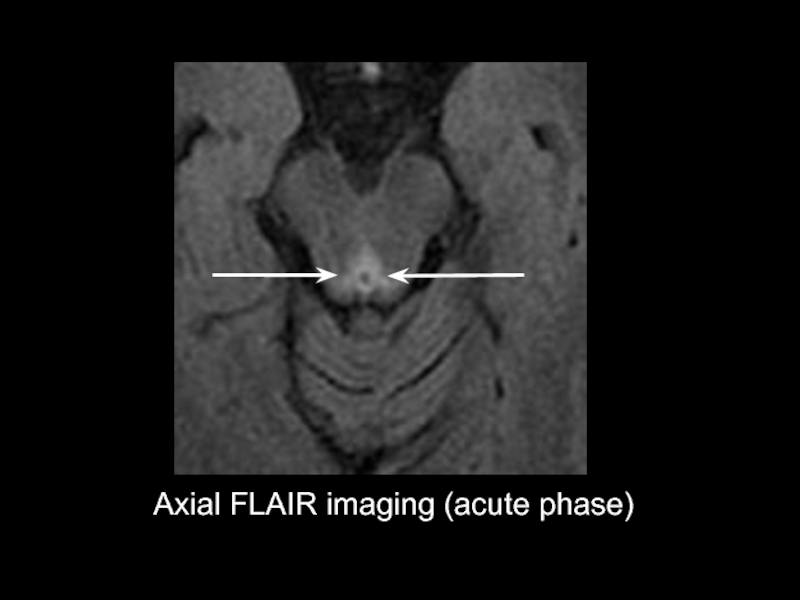

Axial FLAIR imaging (acute phase)

Слайд 4НЕЙРОВИЗУАЛИЗАЦИЯ

Типичная МР картина

Очаги гиперинтенсиного сигнала на Т2/FLAIR

1.Симметрично вокруг водопровода,

2.В области

III желудочка

3.В области медиальных отделов таламуса

На Т1 ВИ увеличение сосцевидных тел (типично для ЭГВ алкогольного

генеза)

Редко(характерно для ЭГВ неалкогольного генеза)

1.Дорсальной часть ствола мозга

2.В области ядра подъязычного нерва

3.В мозжечке

4.Вокруг IV желудочка

5.Конвекситально